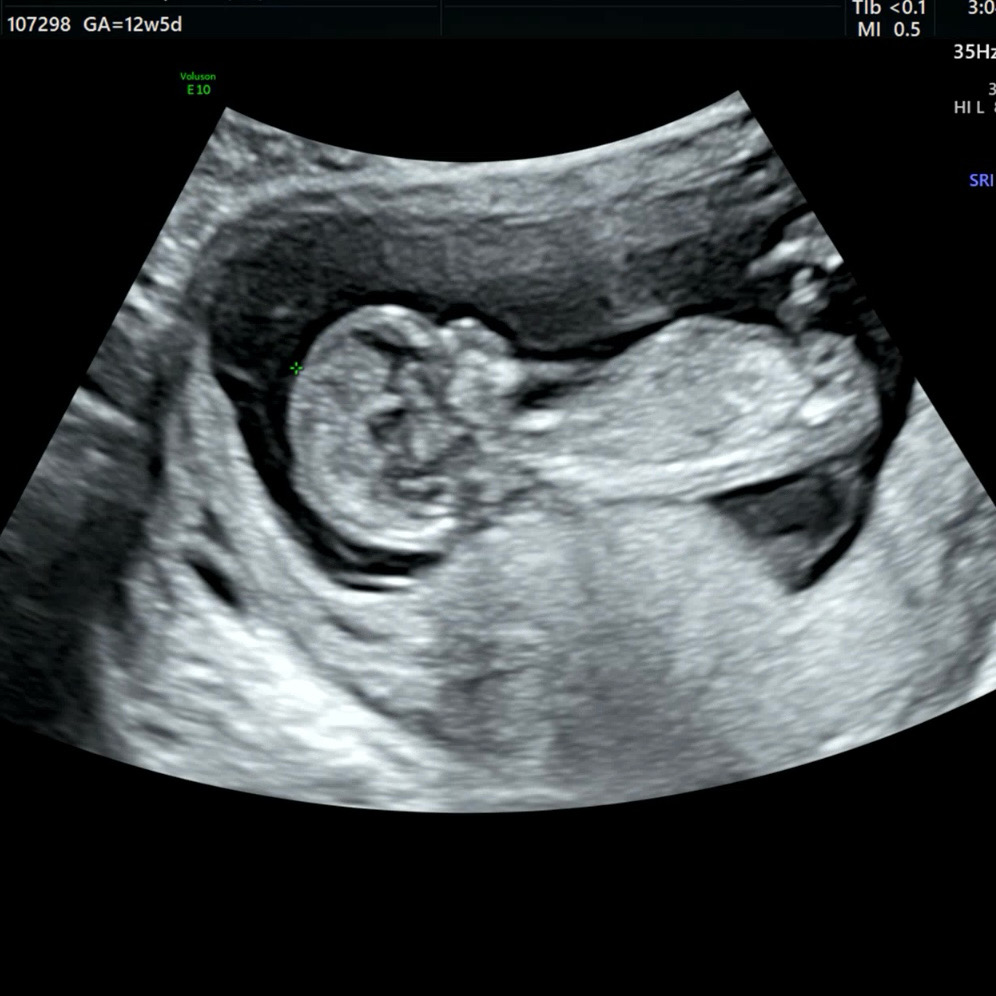

12주5일 초음파! 각도법 고수님들 의견 여쭤봐요ㅎㅎ

오늘 12주 1차 기형아검사 하고 왔어요 ㅎㅎ 혹시 이 사진으로도 각도법 가능할까요…? 각도법 고수님들 의견 부탁드려요>_<